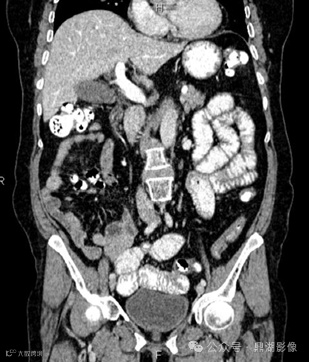

CT小肠造影如下

口服造影剂后CT平扫

CT小肠造影显示回肠袢轻度扩张,回肠皱襞增多、空肠皱襞减少,并伴有多个肠系膜淋巴结肿大。未发现肠套叠、狭窄或肿块形成等征象。